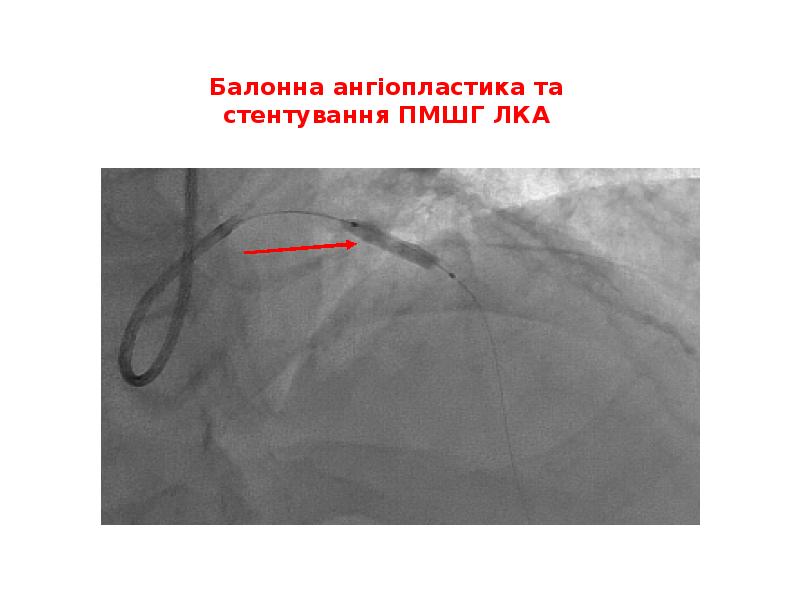

- 45. Балонна ангіопластика та стентування ПМШГ ЛКА

- 46. ТІМІ-3 кровоплин в ПМШГ ЛКА відновлений